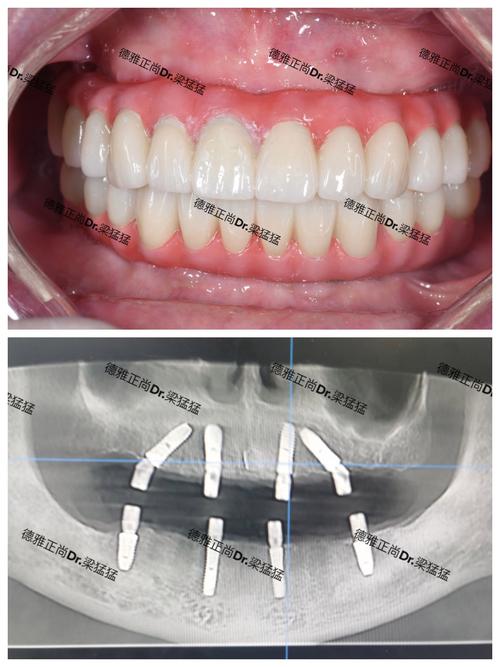

种植牙的核心在于“骨结合”——种植体与牙槽骨之间形成牢固的生物学连接,这种连接不仅能提供强大的咀嚼力,还能刺激牙槽骨避免萎缩,从而维持口腔健康的基础,与活动假牙、固定桥等传统修复方式相比,种植牙的优势尤为突出:它不需要磨损邻牙,支持力更强,使用寿命更长,且外观、触感与自然牙高度相似,真正实现了“以假乱真”的效果。

种植牙的材料选择直接关系到其安全性和使用寿命,种植体多采用纯钛或钛合金,这两种材料具有极佳的生物相容性,能与人体骨骼组织无缝融合,不会产生排异反应;牙冠则以全瓷材料为主,其色泽、通透度和硬度接近天然牙,且不含金属,不会导致牙龈黑线或过敏,美观度和安全性兼顾,随着材料技术的进步,部分高端种植体还采用了表面处理技术(如喷砂酸蚀、阳极氧化),可增加种植体与骨组织的接触面积,促进骨结合,缩短愈合时间。

“获得新生”是种植牙带给缺牙患者的最大感受,功能上,种植牙的咀嚼效率可达90%以上,能轻松咀嚼坚果、肉类等硬物,让患者重新享受美食的乐趣;美观上,牙冠可根据邻牙的形态、颜色定制,修复后笑容自然,不会暴露金属边缘,彻底告别“缺牙尴尬”;健康上,种植体独立存在于牙槽骨中,不磨损邻牙,同时通过生理性刺激维持牙槽骨密度,避免面部塌陷;心理上,摆脱了活动假牙的异物感、脱落风险和发音障碍,患者能更自信地参与社交活动,生活质量显著提升。